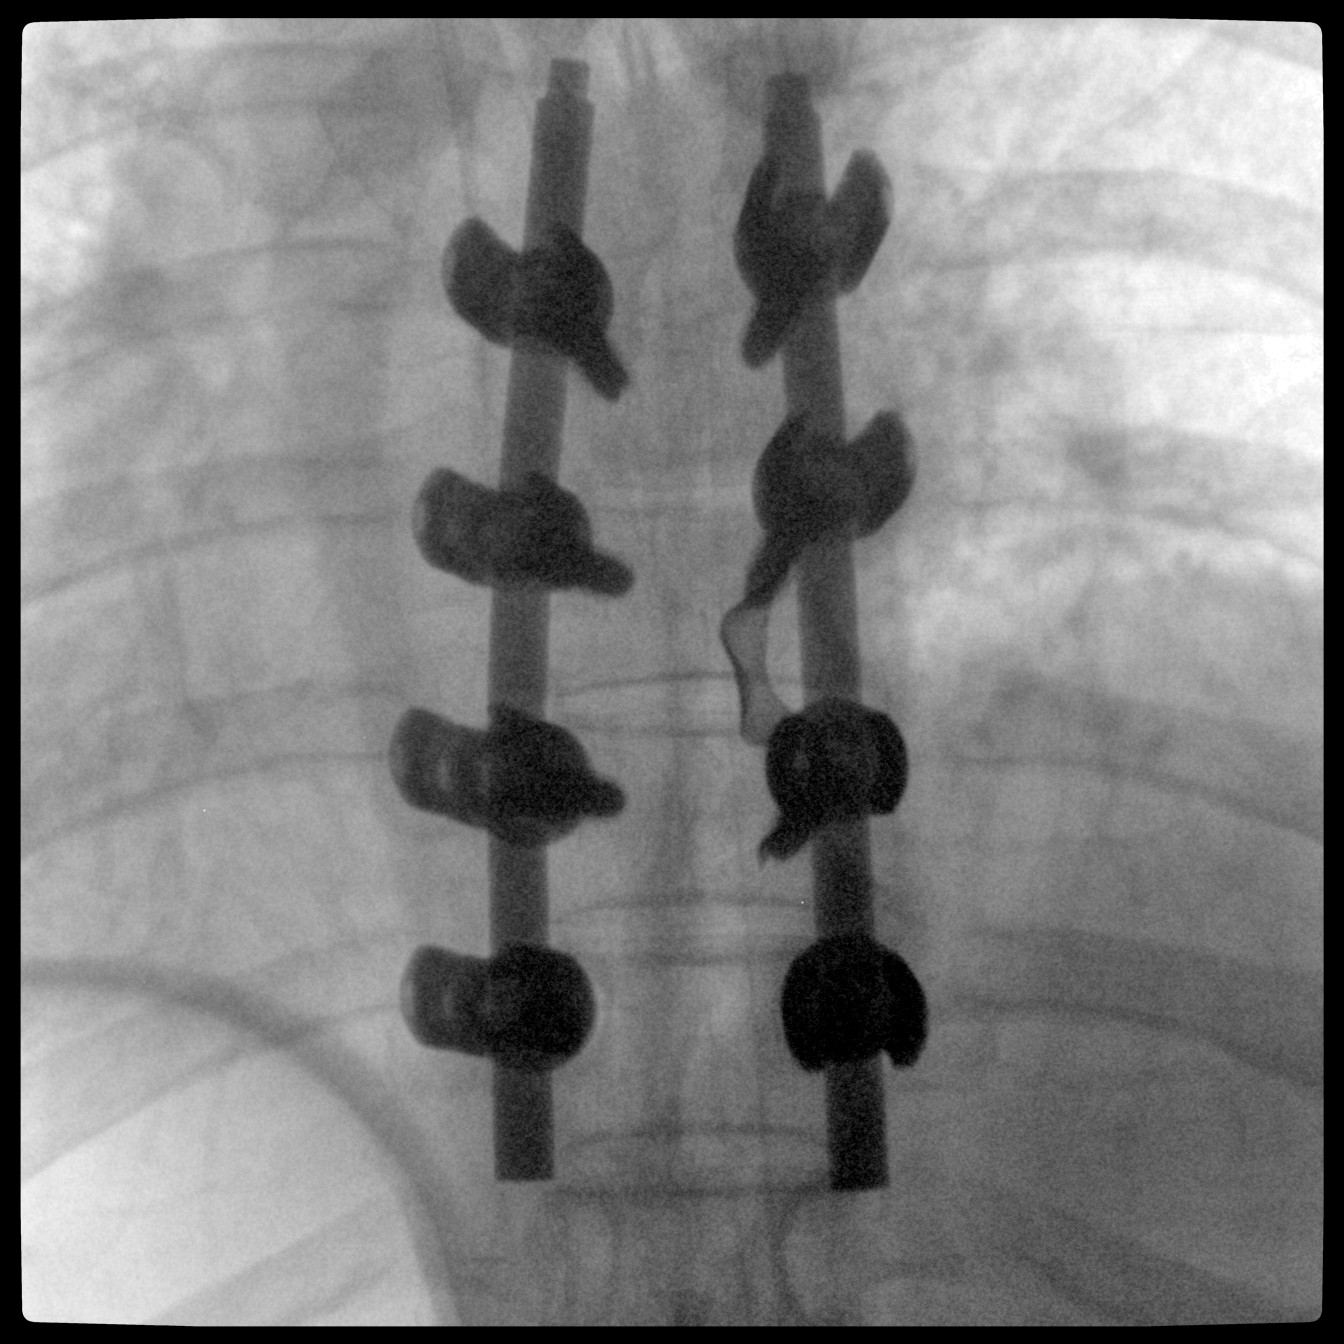

PLX118F-Plus配備了兩種平板尺寸,大尺寸動(dòng)態(tài)平板探測(cè)器成像面積較傳統(tǒng)平板探測(cè)器提升了25%以上,在視野需求大的手術(shù)中,便于醫(yī)生更好定位病灶點(diǎn),規(guī)劃手術(shù)方案,減少因視野范圍不足而多次透視、點(diǎn)片造成的不便。